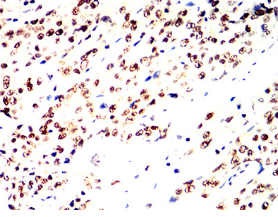

IHC    1/200 - 1/1000